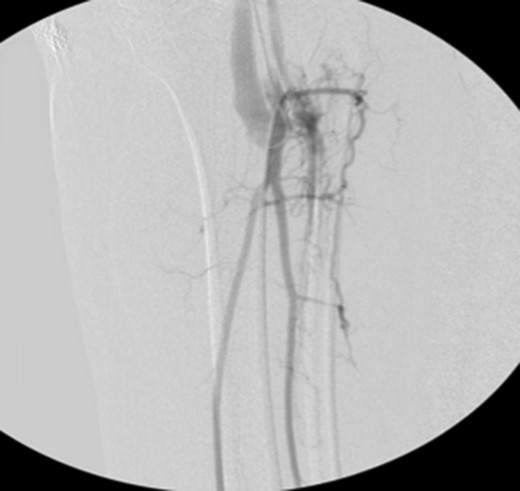

Patient underwent a left lower extremity angiogram. During the procedure she was found to have patent aorta and bilateral common iliac artery. There was no disease visualized in the left external iliac artery, common femoral artery (CFA), SFA, patent previously placed stent, patent above and below the knee PA and two vessel run off to the foot (Fig. 1). Upon delayed fluoroscopic images we identified contrast filling the deep venous system rather quickly suggesting a high volume fistula (Fig. 2). We then identified the fistula between ATA and ATV. Although ATA was previously ligated there was retrograde filling of the artery from unnamed branches, which communicated with the venous system as shown in. In the midcalf (ATA) was cannulated with a micropuncture needle. Micropuncture wire was inserted and a 5-Fr sheath was inserted after exchanging over wire. At this point VortX coils (Boston Scientific) were placed from the curve of ATA until the whole AVF was sealed. Anterograde angiogram showed no flow through the fistula (Figs 3 and 4). There was a palpable PT and DP pulse at the completion of the procedure. Sheath was removed, pressure dressing applied. Patient was discharged home same day. Recovery has been unremarkable. Three months follow-up claudication symptoms have significantly improved.

Fluoroscopy imaging showing high volume anterior tibial artery to vein iatrogenic fistula.